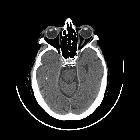

CT

Scleral plaques appear as small ovoid calcifications along the anterior globe, at the site of insertion of the medial and lateral rectus muscles .